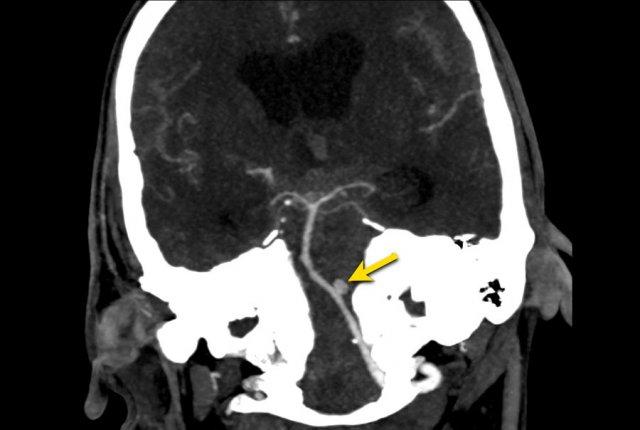

Các hình ảnh cho thấy xuất huyết dưới nhện do vỡ phình động mạch não giữa bên trái (mũi tên).

Hình ảnh CT của bệnh nhân SAH tự phát.

CTA được thực hiện để tìm kiếm phình động mạch.

Lưu ý có hai túi phình động mạch (mũi tên):

- Xoang cảnh (carotid siphon)

- Động mạch não giữa

Cả hai đều được điều trị bằng can thiệp nút coil.